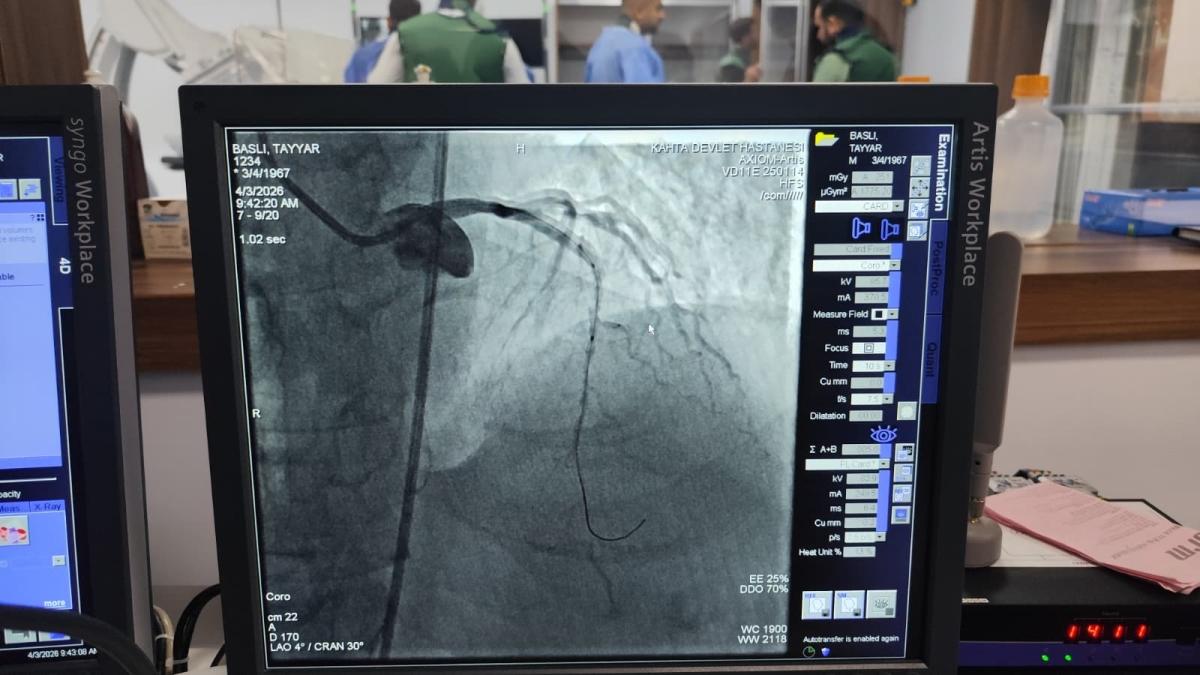

Edinilen bilgilere göre, kalp krizi şüphesiyle Kahta Devlet Hastanesi Acil Servisi'ne başvuran 59 yaşındaki hasta, yapılan ilk müdahalenin ardından vakit kaybetmeden anjiyo ünitesine alındı. Burada gerçekleştirilen operasyon sırasında hastanın kapalı olduğu belirlenen iki damarına stent takıldı.

"Hastanemizden 45 kilometre mesafede ikamet eden 59 yaşındaki hastamız, göğüs ağrısı şikâyeti ile hastanemize başvurmuştur. Yapılan tetkiklerde kalp krizi geçirdiği tespit edildi ve acil bir şekilde yeni açmış olduğumuz anjiyo merkezimize hastayı aldık. Yapılan görüntülemede kalbin ön damarı olan LAD mid bölgesinin total tıkalı olduğu tespit edildi. Hastamızın ön damarına iki adet stent takarak tam açıklık sağlandı. Hastamızın genel durumu iyi olup takip amacıyla yoğun bakıma alındı."